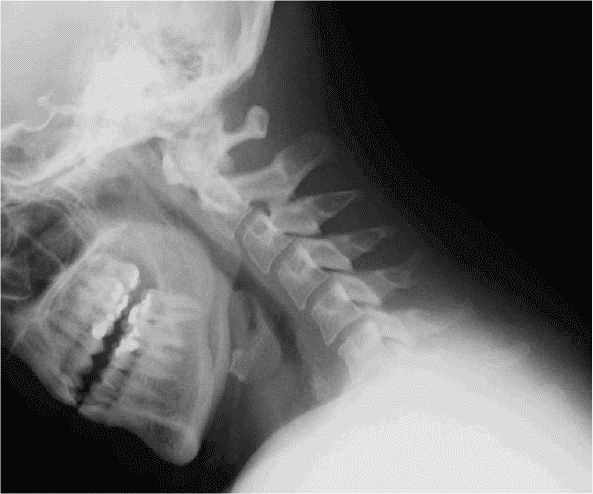

C1/C2 BOUCHE OUVERTE

– – Le patient est assis ou debout

– – Il est antéro-postérieur

– – Il doit ouvrir la bouche le plus possible

RAYON DIRECTEUR

– – Il est centré au raz des incisives supérieures

VARIANTES

– – En décubitus dorsal